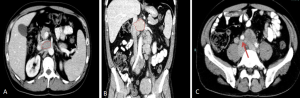

- Genitourinary tuberculosis commonly affects the kidneys, ureters, bladder, and prostate, usually unilaterally. Renal findings include parenchymal oedema and hypoperfusion manifesting on CT as geographic areas of parenchymal hypoattenuation that mimic acute pyelonephritis and abscess (acute tuberculous renal abscess are 10-40 HU with mild peripheral enhancement) in the active inflammation, calyceal erosions, papillary necrosis, parenchymal cavitation, and calcifications in the chronic phase, potentially progressing to autonephrectomy. Ureteric involvement presents as wall thickening and strictures, predominantly in distal segments, leading to hydroureteronephrosis.